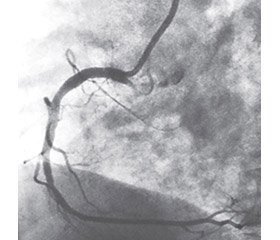

Для візуалізації коронарного кровотоку і визначення впливу лідокаїну на функціональний стан коронарних судин використовувалася методика коронарографії.

Відповідно до проведених нами досліджень, внутрішньокоронарне введення лідокаїну (яке проводилося з метою профілактики життєзагрожуючих аритмій при стентуванні коронарних артерій), не тільки не викликало спазму вінцевих судин, але й сприяло їх дилатації (рис. 2, 3).